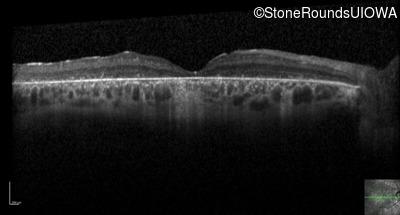

Optical Coherence Tomography - Left - 10/160 -1

Exemplar / OCT Stack